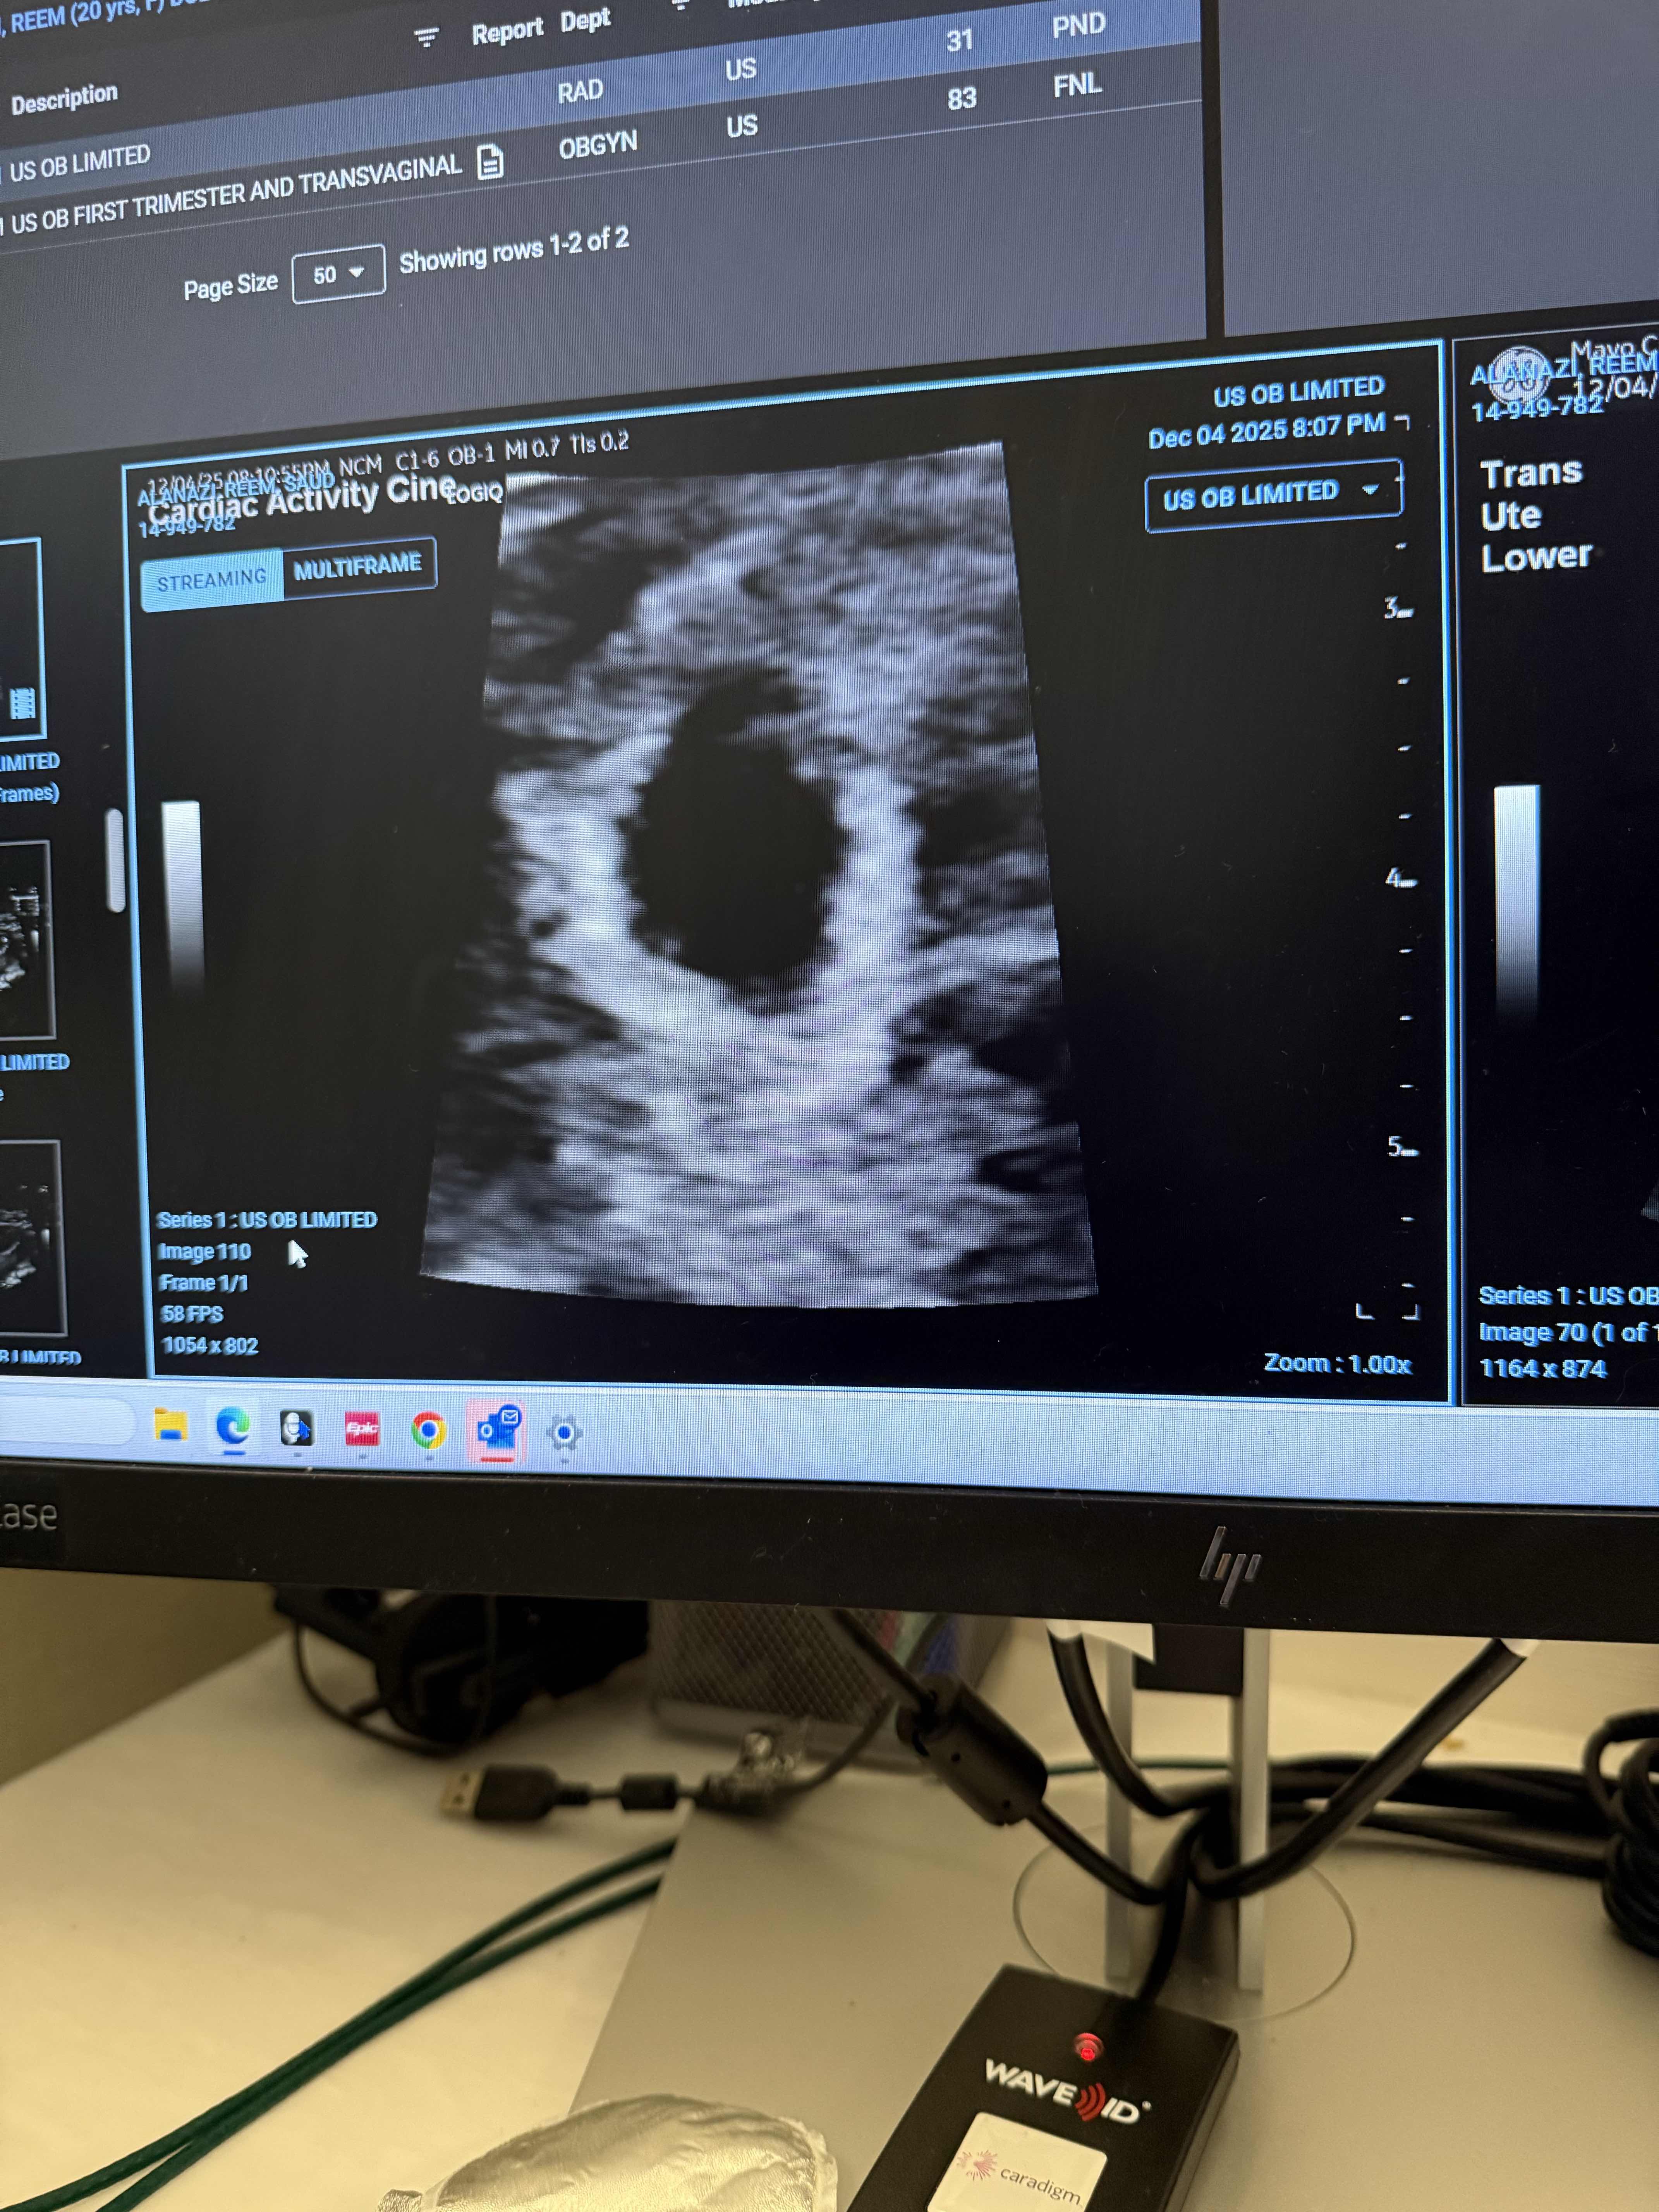

ينصح بوقف العلاقة وراحة من اي مجهود شاق واعادة السونار بعد ١٠ ايام للتاكد من حالة الحمل ولا داعي لاي مثبت مع تناول اقراص حمض الفوليك فقط والمتابعة